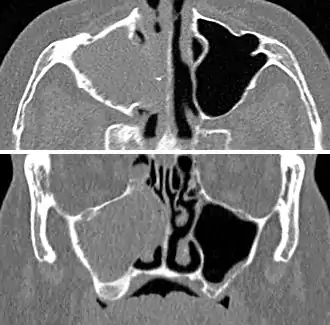

| A CT scan showing sinusitis of the ethmoid sinus | |

For sinusitis lasting more than 12 weeks, a CT scan is recommended.[54] On a CT scan, acute sinus secretions have a radiodensity of 10 to 25 Hounsfield units (HU), but in a more chronic state they become more viscous, with a radiodensity of 30 to 60 HU.[56]

CT of chronic sinusitis

CT scan of chronic sinusitis, showing a filled right maxillary sinus with sclerotic thickened bone.